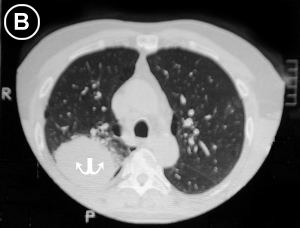

• Corte Tomográfico

en tercio superior del tórax:

• Flechas Blancas: Lesión pulmonar, redondeada, sólida y de bordes irregulares, adosada aparentemente a la pared torácica posterior.